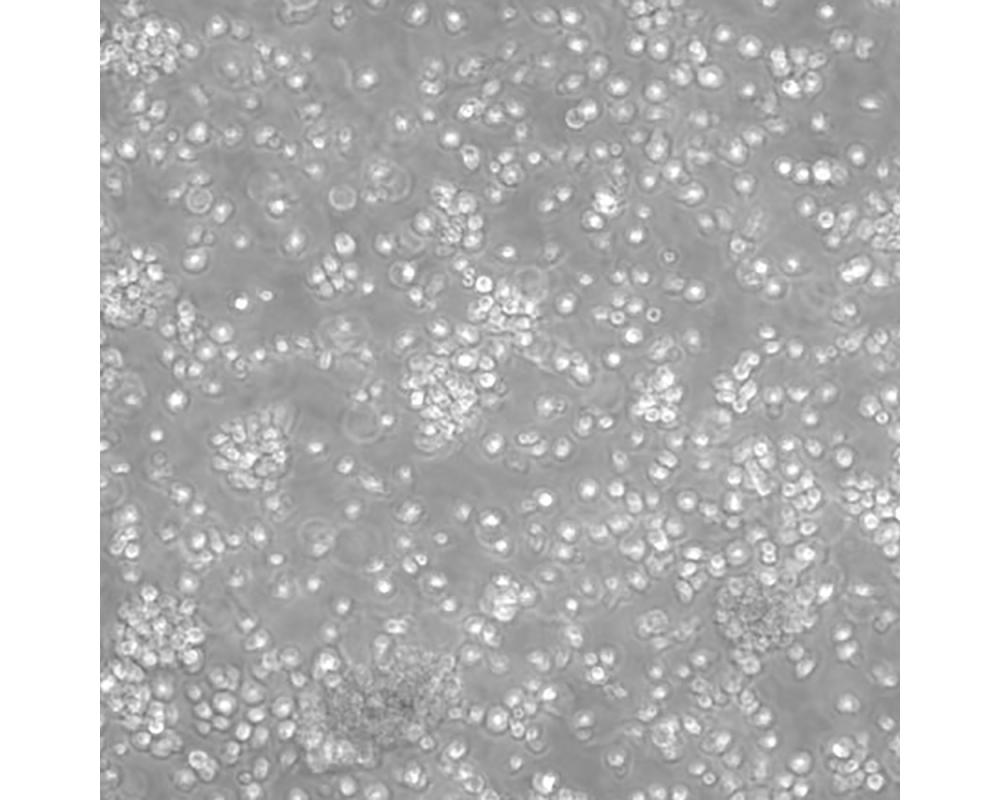

CCRF-SB

中文名稱 人急性T淋巴細胞白血病細胞

組織來源 急性T淋巴細胞白血病;男性

生長特性 懸浮